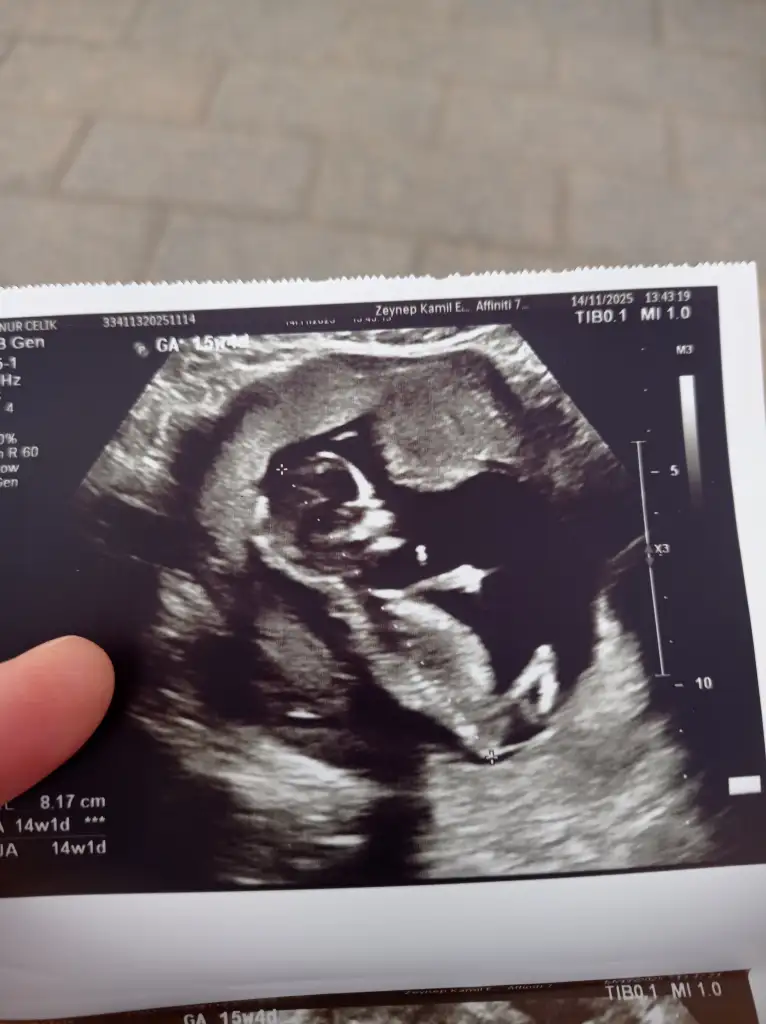

Ayy beni de sora bilirmisiniz acaba? Tahmin var ama merak etdim ne diyeceğini)

38,1 KB · Görüntüleme: 90

28,2 KB · Görüntüleme: 77